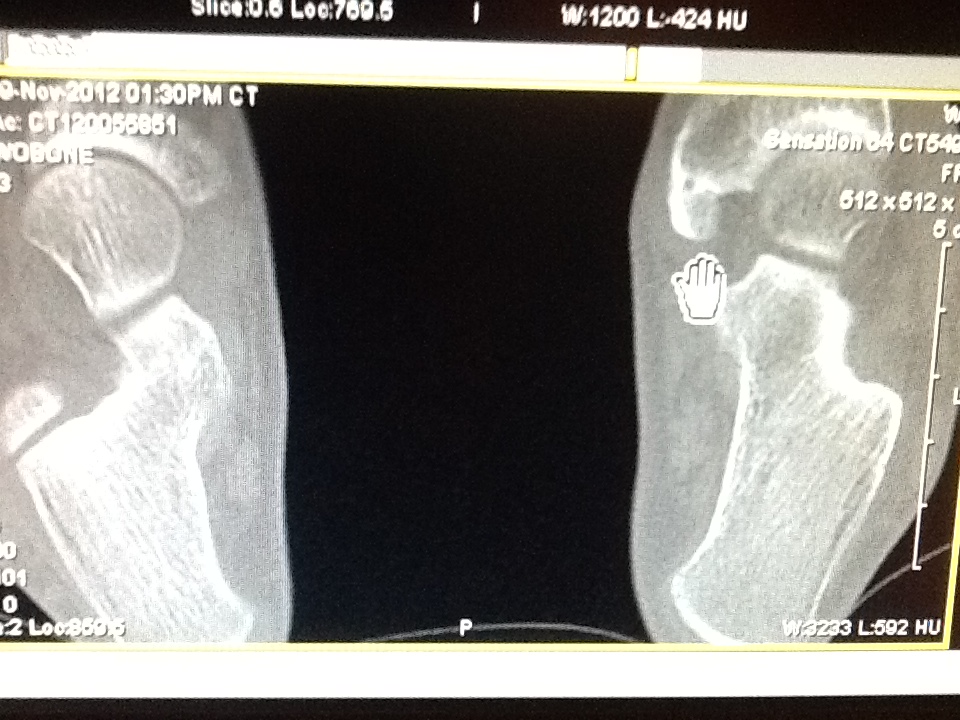

6 wk post op of reconstruction post tibial tendon with excision accessory navicular, osteotomy

6 wk post op of reconstruction post tibial tendon with excision accessory navicular, osteotomy Surgery Accessory Navicular The accessory navicular (os tibiale externum) is an extra piece of cartilage or bone located midfoot just above the arch on the inside of the foot. Acessory navicular is a common idiopathic condition of the foot that presents with an enlargement of the navicular bone. For patients who have failed conservative care or who have recurrent symptoms, surgery can be. Surgery Accessory Navicular.